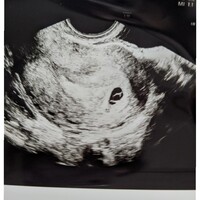

IVFでこの度、初めての陽性反応出ました。 昨日、陽性判定後10日目の診察に行ったところ ・6W1D(排卵日が確定しているので間違いない) ・卵黄嚢確認 ・心拍確認(動いてるのは私にも確認出来ました) 胎嚢の大きさは115mmとのこと。 先生は笑顔でしたし、 『次は10日後で。今日 (6w1d)心拍確認できました^ ^♡ 心拍確認まで心配で心配で。 一山超えました! ! でも心拍確認した後上手くいかない場合もあるので油断できないですね。 。 。 今日のブログでは妊娠発覚から心拍確認までまとめてお話ししようかと思います はじめまして。 大阪出身のmeiです。 30代の管理栄養士で、保育園→クリニック→病院で勤務経験があります。 更に"食"の道を追求するため野菜ソムリエの資格を取得し、フリーランスとして新たな道を歩もうとしていた矢先に、産婦人科での検査で問題が

6週で心拍が見えるなんて順調ですね、と言っていただけました。 心拍が見えたのでやっと安心できます。 心拍確認ができれば流産の確率はぐっと下がる、って言いますよね。 エコー写真と分娩予約の紙などをもらい、診察終了。 次回は3週間後です。